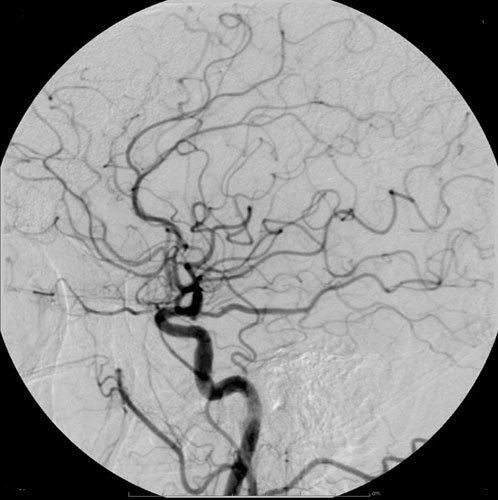

What’s DSA?

Use in the diagnosis of arterial/venous occlusions, arterial stenosis, PE, to diagnose renal artery stenosis (standard procedure in donations), aneurysms, AVM